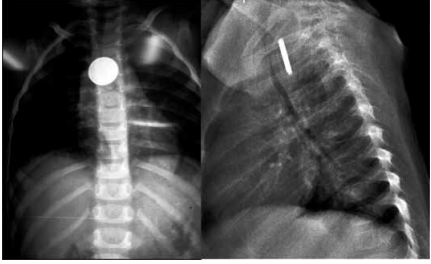

Menina de 3 anos, há uma hora, engoliu um corpo estranho enquanto brincava sozinha em seu quarto. Ninguém presenciou a ingestão. Desde então, apresenta disfagia, sem sialorreia e sem nenhum outro sintoma. As radiografias de tórax realizadas estão apresentadas na imagem a seguir.

(Arquivo pessoal; imagem usada com autorização)

A conduta é: